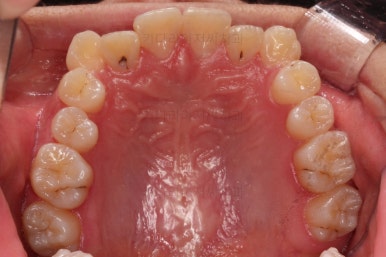

충치가 곳곳에 보이는데요.

성인들은 충치가 멈춰있는 정지우식일 가능성도 있으며 크기가 현재 크지 않고 향후 변화되지 않는다면 그대로 두기도 합니다.

이번 환자분도 교정치료에 방해되는 부분이나 급해보이는 추료만 우선 진행하고 교정 중에 충치가 커지는지 증상이 생기는지 관찰해 보기로 했습니다.